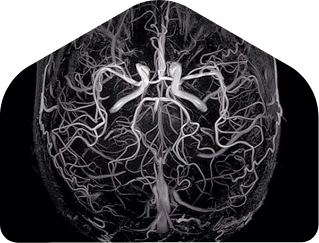

What are brain aneurysms?

Advanced Treatment Options for Brain Aneurysms

We offer a full range of advanced, minimally invasive treatments for brain aneurysms. Our expert team combines leading-edge technology with compassionate care to ensure every patient receives the safest and most effective treatment plan.